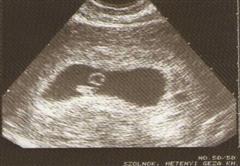

Számold ki kalkulátorral. Én orvosnál 5+6 nál voltam, uh-on meg 6+0-nál, és már látszódott 4 mm-es élő embrió, kis pulzáló szívecskével (vagy szívkezdeménnyel, na ezt pontosan nem tudom).

csajok, bemutatom nektek Papp (Bogyókát):